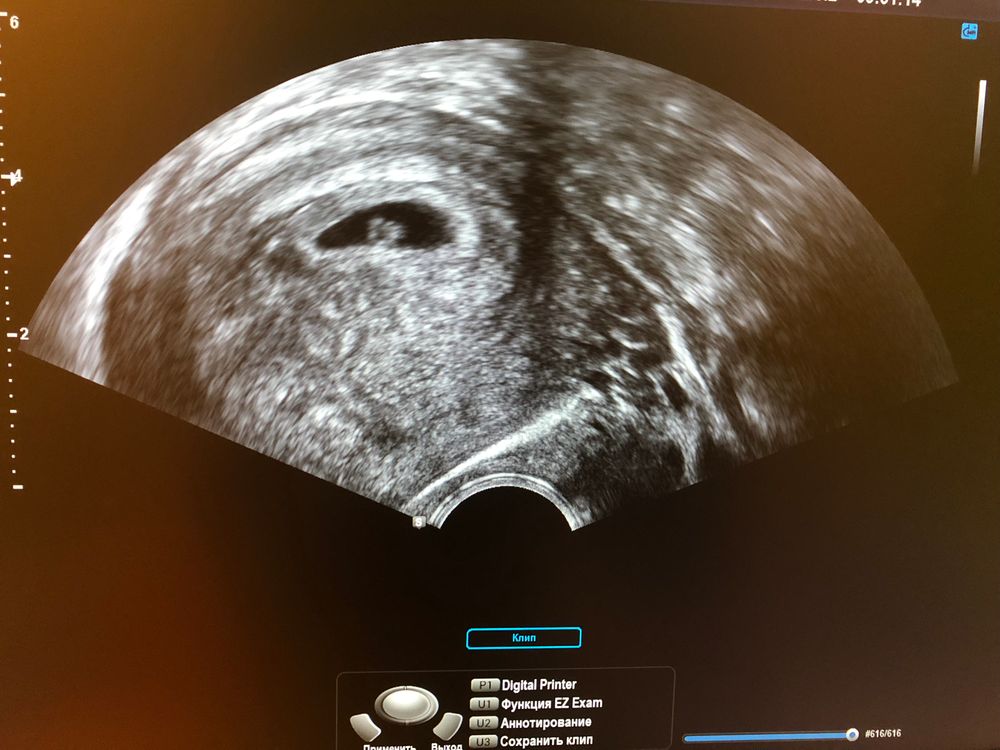

Первое УЗИ 🤰🏻

Поздравляю 🤗🤗🤗помню свое первое узи) фотка распечатана лежит) один из самых первых трепетных моментов) точечка с сердечком) такой маленький человек и такое большое чудо)